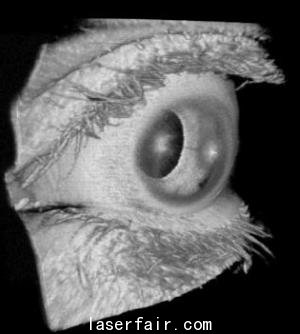

實際的例子很多,比如眼科。1.2 MHz的A-掃描速率可以在病人眨眼或者不由自主地移動眼睛之前就可以完成對視網膜的大範圍掃描。另一個(ge) 實例就是癌症研究,使用微型OCT探針,可以1 MHz的A-掃描速率完成兔食管、結腸和胃的成像。這意味著,該技術在使用這種可調諧VCSEL實現人體(ti) 內(nei) 窺鏡癌症成像的應用領域取得了進步。

Potsaid說:“已經證實,在眼科成像中,這種VCSEL可以580 kHz的A-掃描速率、83 nm的波長調諧範圍及8.9 μm的軸向分辨率對視網膜進行掃描,提供適合視網膜成像的成像範圍。掃描前眼需要更長的成像範圍,但是,通過降低VCSEL的掃描速率,同時保證相同的光譜掃描範圍,則可以在犧牲分辨率的情況下實現前眼掃描。”

在對眼睛的整個(ge) 長度進行成像方麵,可以更進一步將VCSEL的掃描速率降到50 kHz,波長調節範圍減小到45 nm。這樣做,分辨率略有下降,但成像範圍足以包括眼睛的整個(ge) 長度,從(cong) 眼角膜到視網膜。